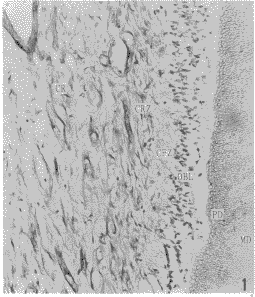

在牙髓中央区,纤维粘连蛋白-IR以条索状和网状两种形式存在,条索状者一般纤维粗大,数量少,多局限于中轴部分,沿血管和神经分布,动脉周围多于静脉。网状者一般较条索状纤维细小,数量多,广泛存在于中轴以外的基质中。从中轴向周边,纤维由粗变细,和致密(图1)。在多细胞区纤维粘连蛋白-IR物略为增粗,呈细条索网,经成纤维细胞之间至乏细胞区。在乏细胞区纤维粘连蛋白-IR物更为细小,无方向性,彼此交织成网,并向成牙本质细胞层延伸。在成牙本质细胞层,纤维粘连蛋白-IR物汇集成束,经成牙本质细胞之间到达前期牙本质(图2)。前期牙本质内的纤维粘连蛋白-IR物尤为丰富,纤维粗大密集,着色深;在成熟牙本质内,纤维粘连蛋白-IR物仅见于牙本质小管与成牙本质细胞突起之间的间隙内,通过小管侧支与相邻牙本质小管内的纤维粘连蛋白-IR物相连。其他成熟牙本质内未见纤维粘连蛋白阳性反应(图3)。用PBS液代替一抗的对照片中未见纤维粘连蛋白的阳性反应物。

图1 牙髓牙本质复合体内纤维粘连蛋白分布.中央区(CR),多细胞区(CRZ),乏细胞区(CFZ),成牙本质细胞层(OBL),前期牙本质(PD),成熟牙本质(MD). ×100

Fig.1 The distribution of fibronectin in dental pulp-dentin complex. center region(CR), cell-rich zone(CRZ),cell-free zone(CFZ), odontoblast layer(OBL), predentin(PD), mature dentin(MD) ×100